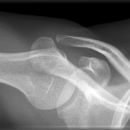

Schulter axial

Beurteilungskriterien